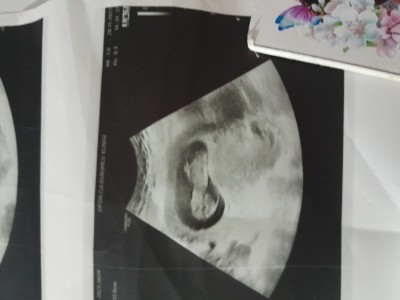

Bir kızdan sonra birde erkek geliyo Allah nasip ederse ,<3Allah'ım isteyen herkese bu duyguyu nasip etsin :)<3 13hafta

Allah'ım hayırlısı ile kucagına almayı nasip etsin inşallah bende bugün gittim söylemedi sende ultrason fotosu var mı paylaşabilir misin burda

Var canım atiyorum 11hafta orda daha belli oluyo

Teşekkür ederim gördüm hayırlısı ile kucagına almayı nasip etsin inşallah